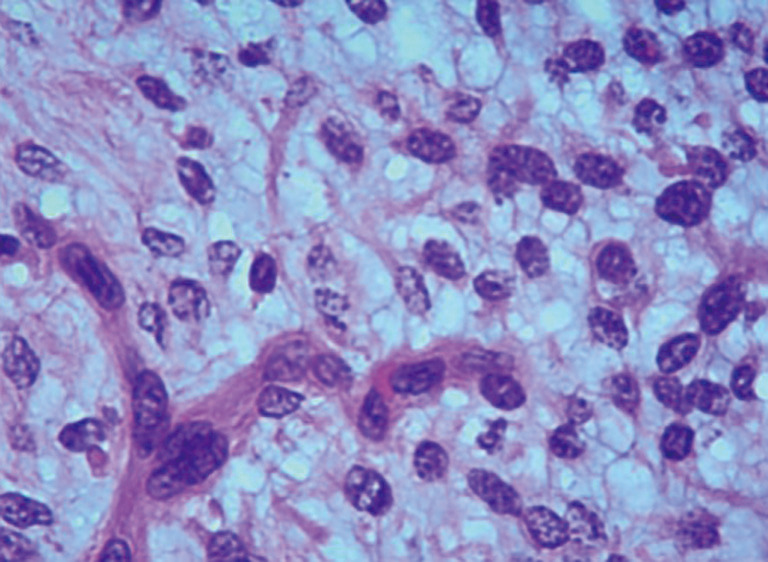

Case description: A 7-year-old Chinese female patient was admitted to Guangzhou Women and Children's Medical Center in October 2023. Due to "pallor for 4 months and the discovery of a tumor in the gastric antrum over 2 weeks ago", an enhancement CT scan revealed a mass in her gastric antrum, approximately 4.0 cm × 3.5 cm × 3.0 cm in size, but its nature remains to be determined. On electronic gastroscopy, a mass was identified in the gastric antrum and pylorus orifice. It exhibited a smooth surface, with its base located on the lesser curvature side and pylorus. We did robot-assisted partial gastrectomy with Billroth I anastomosis for her to remove the mass. Now it has been 11 months after the operation, and the child has recovered well with no sign of mass recurrence.